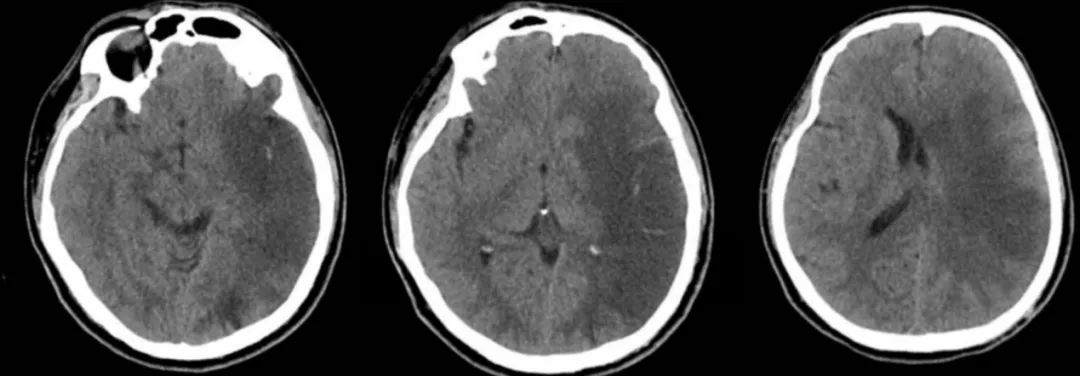

男性59岁,主因头痛发热9天,认知下降5天入院。查体:神志清,反应迟钝,记忆力下降,定向力和计算力检查不合作,肌力和肌张力基本正常。

答案:单纯疱疹病毒性脑炎。复查后如下:

单纯疱疹病毒性脑炎(HSE)是由单纯疱疹病毒(herpessimplexvirus,HSV)感染引起的一种急性CNS感染性疾病,又称为急性坏死性脑炎。HSV有两种血清型,即HSV-1和HSV-2。在人类大约90%HSE由HSV-1引起。仅10%由HSV-2所致,且HSV-2所引起的HSE主要发生在新生儿,是新生儿通过产道时被HSV-2感染所致。神经节中的神经细胞是病毒潜伏的主要场所,HSV-1主要潜伏在三叉神经节,HSV-2潜伏在骶神经节。当人体受到各种非特异性刺激使机体免疫力下降,潜伏的病毒再度活化,通过嗅神经和三叉神经侵入脑策划,常选择性损害额叶基底部和颞叶,不损害豆状核。临床常见症状有:头痛、呕吐、轻微的意识和人格改变、记忆丧失、轻偏瘫、偏盲、失语、共济失调、癫痫发作、多动(震颤、舞蹈样动作、肌阵挛)、脑膜刺激征等。精神行为异常可为首发或唯一症状。单疱病毒性脑炎MR表现以双侧颞叶、额叶受累为主,脑岛及海马均受累,病变均与豆状核分界清楚,以外囊为界。